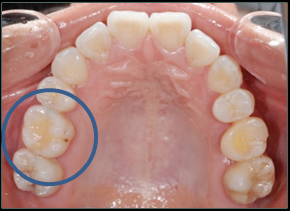

【親知らずを欠損部に移植した例】

【のう胞を伴った歯の再植例】

一度歯を抜いて、のう胞を摘出して再植しています。